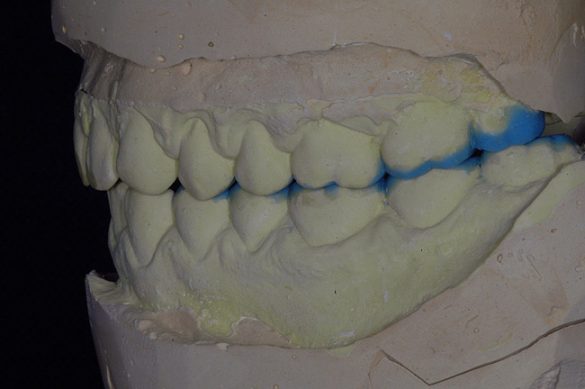

După tratamentul cauzelor GERD, s-au înregistrat amprente din alginat iar modelele din gips rezultate au fost montate pe un articulator semiajustabil. Ariile ce urmau a fi restaurate au fost modelate din ceară, pentru analiza diagnostică a relaţiei ocluzale dorite. Apoi s-a creat o lingură semirigidă din acetat pentru a servi ca şablon în timpul procedurii restauratoare. Potrivit analizei modelelor montate în articulator, înălţimea minimă pentru restabilirea dimensiunii verticale de ocluzie era de 1,5mm (fig. 4).